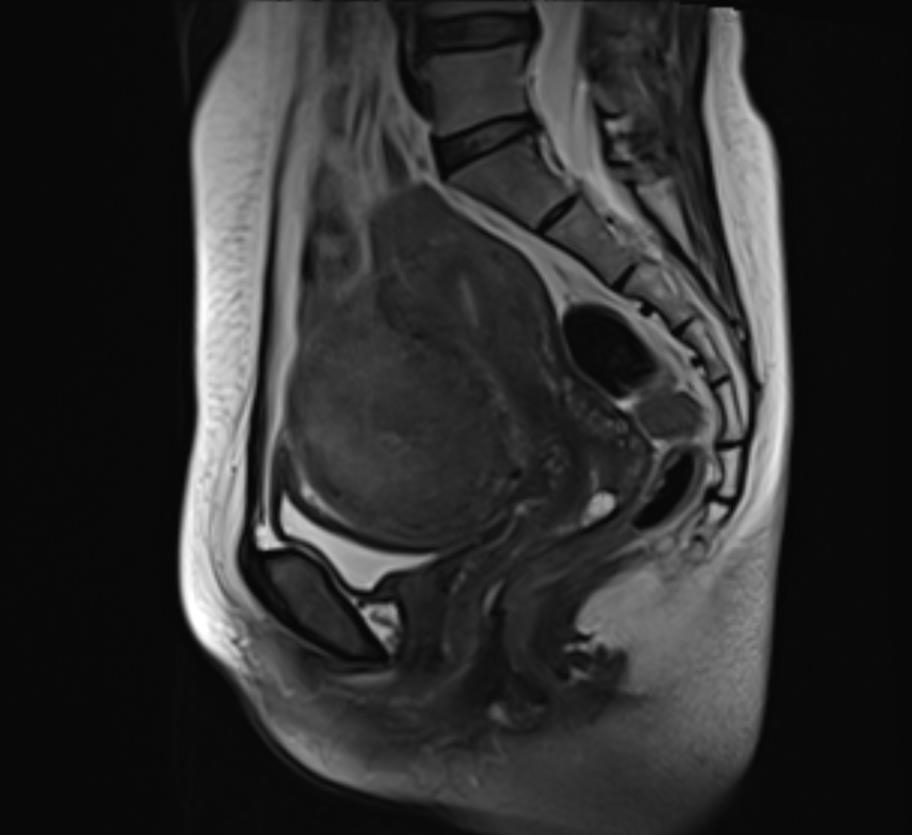

确定好手术时间后,盛女士在家人陪同下提前入住我院妇产科。经入院彩超检查和盆腔MRI平扫提示,子宫肌瘤直径达到了8cm,已经压迫膀胱,需尽快手术。